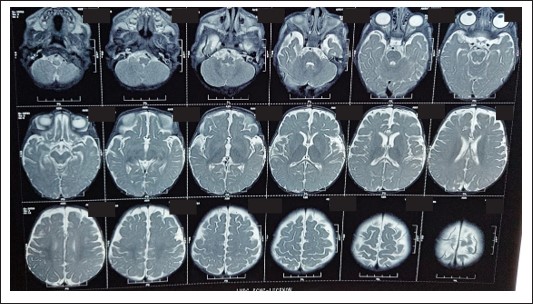

Figure 3: MR T2WI image shows mild cerebral atrophy in the form of prominent sulcal spaces, cisterns without obvious white matter volume loss..

HRCT revealed consolidations in bilateral upper and lower lung lobes with mild hepatosplenomegaly and borderline cardiomegaly MRI Brain revealed: cerebral atrophy, thinning of corpus callosum and symmetric DWI restriction in globus pallidi, PLIC, peritrigonal white matter, optic radiations, brainstem and medial temporal gyri (which raised the suspicion of INBORN ERROR OF METABOLISM).